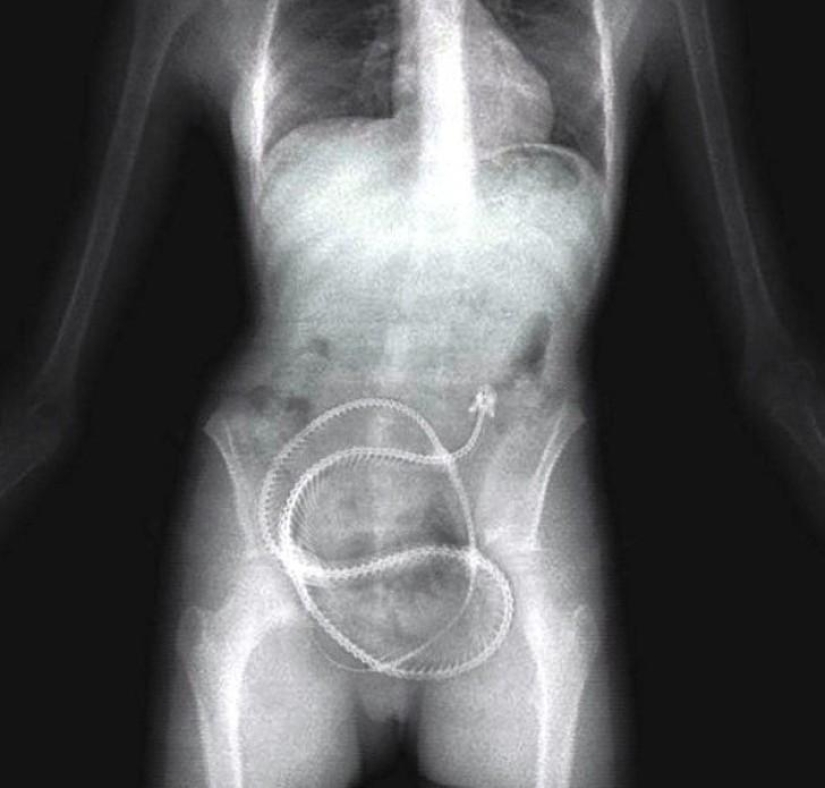

Enorme ovillo de lana.